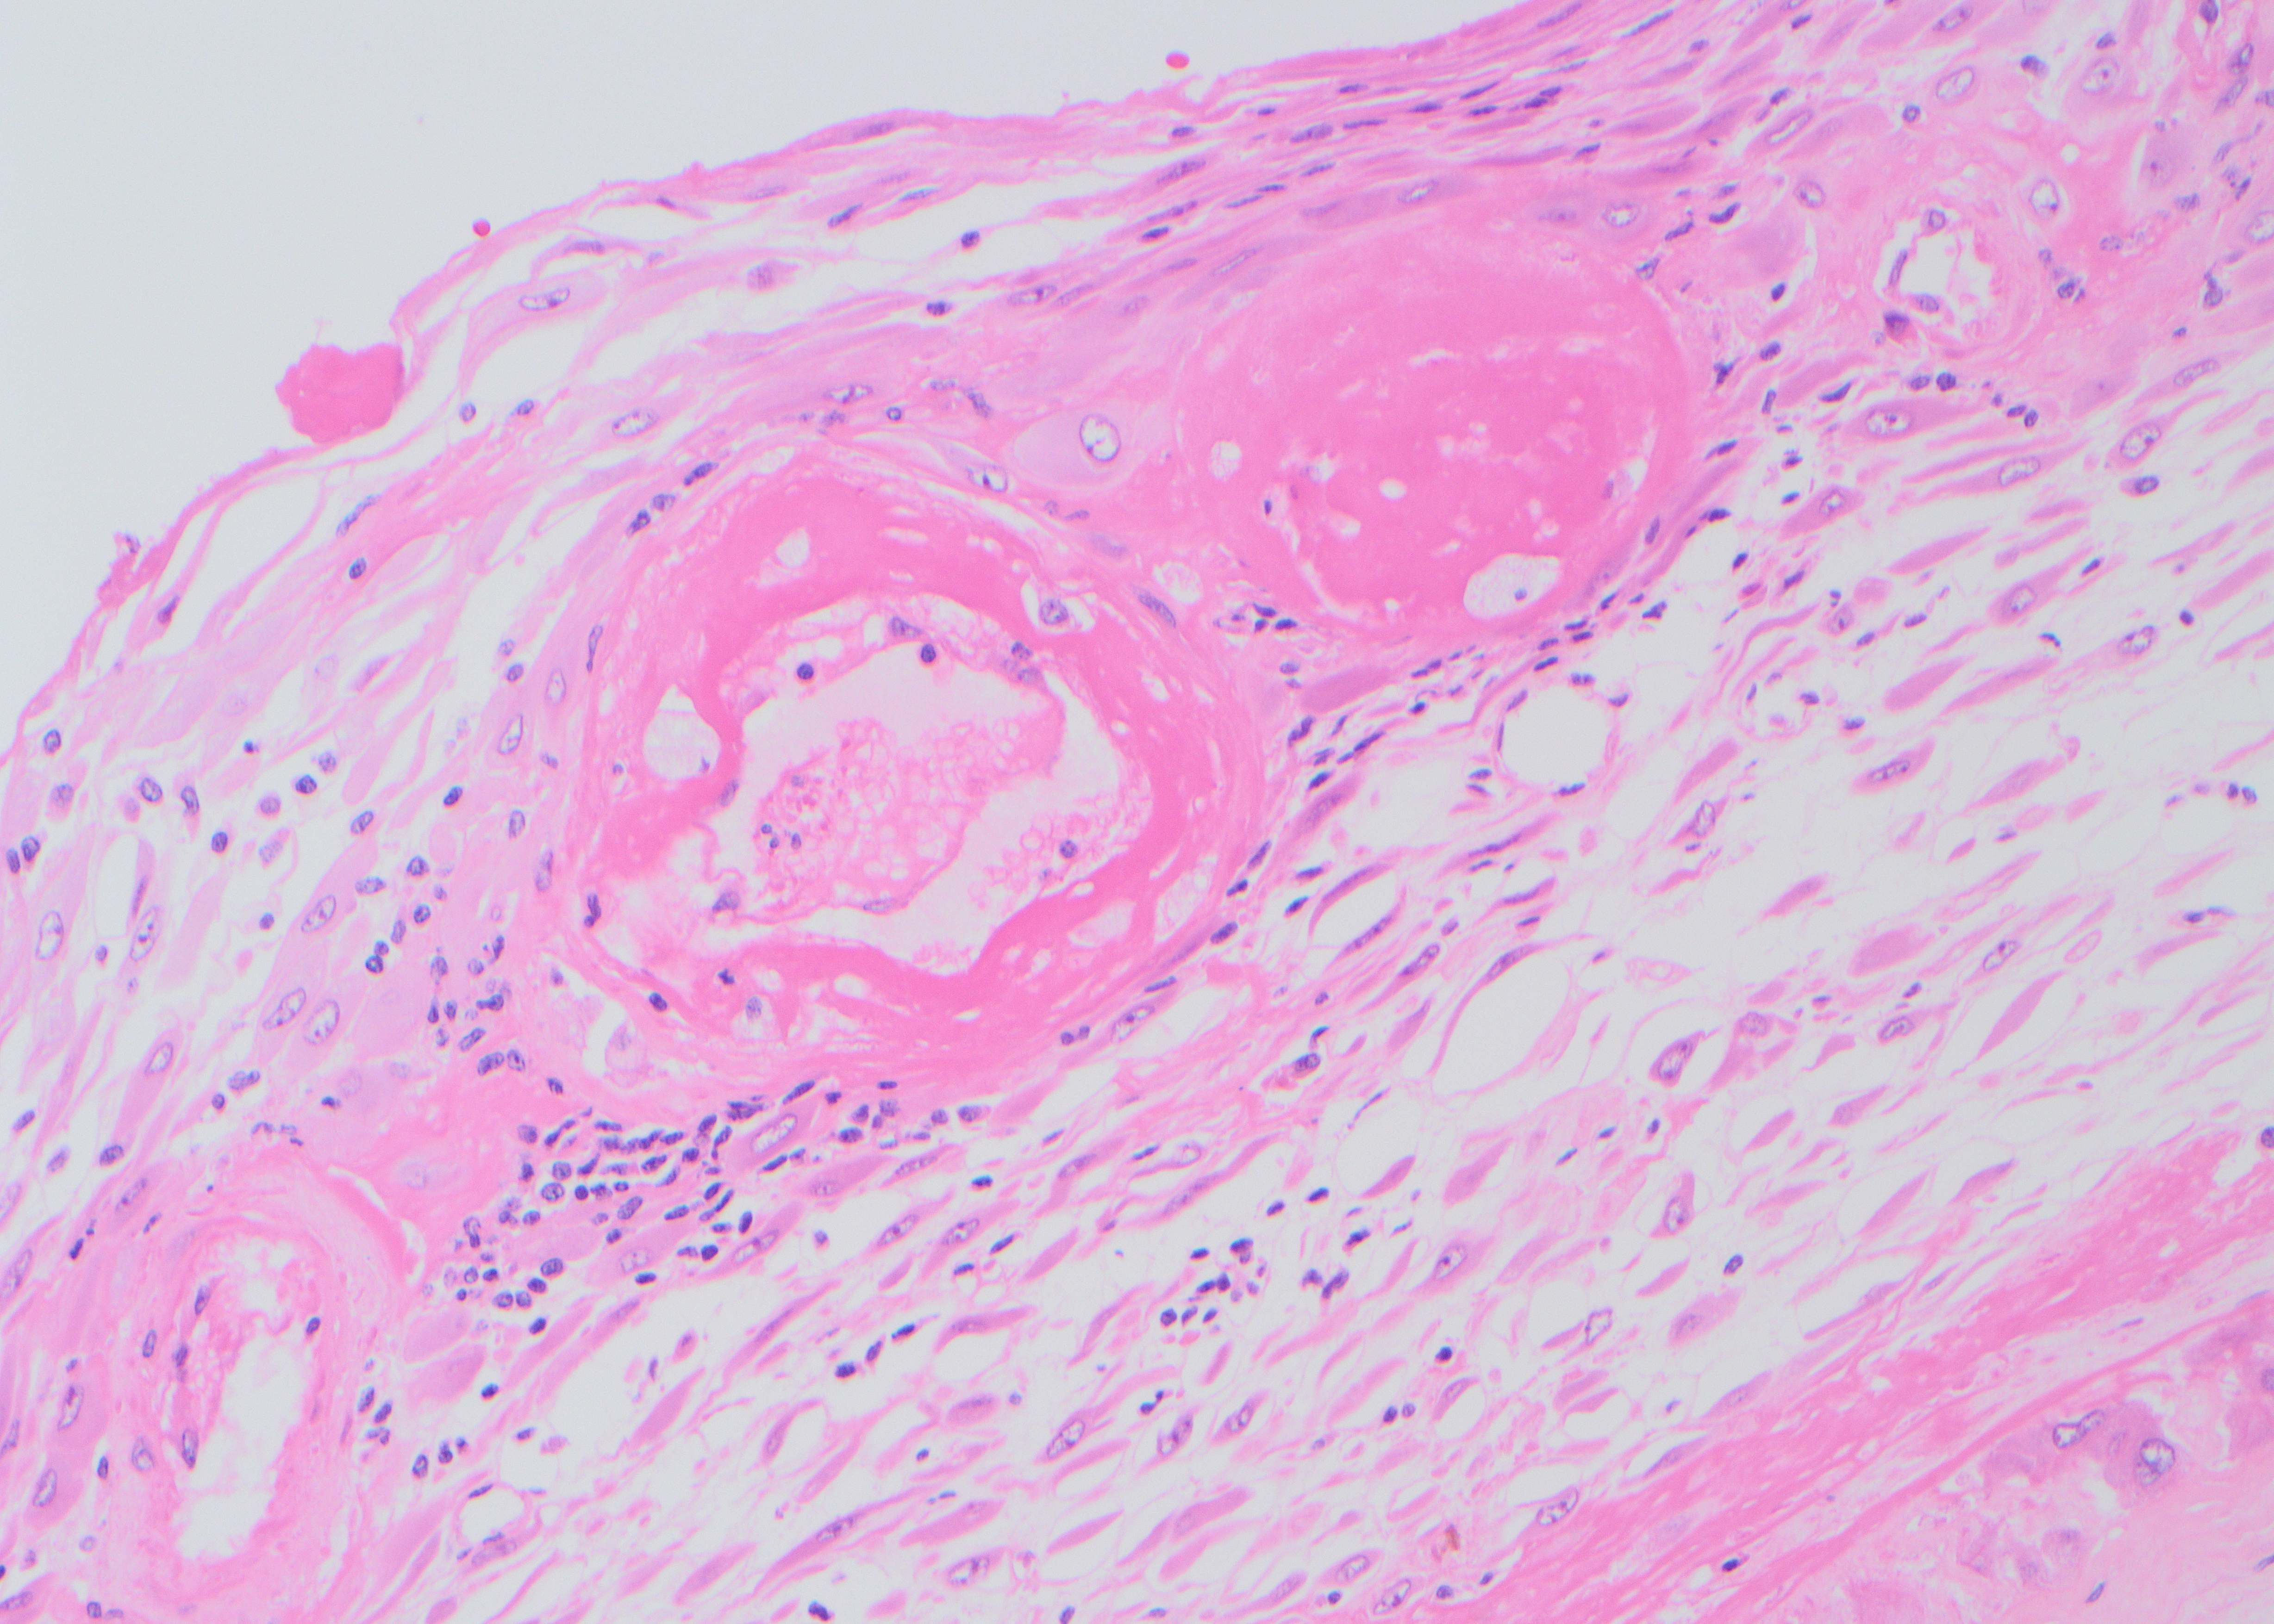

A 64 year-old man with history of clear cell renal cell carcinoma s/p nephrectomy (2021) presents with scrotal pain and firmness. Ultrasound reveals a 2 cm solid lesion. Serum tumor markers (hCG and AFP) were normal. The tumor was negative for SALL4, OCT3/4, AFP, and showed focal patchy positivity for pancytokeratin (focal). PAX8 was weakly positive. Additional stains are displayed in the pictures.